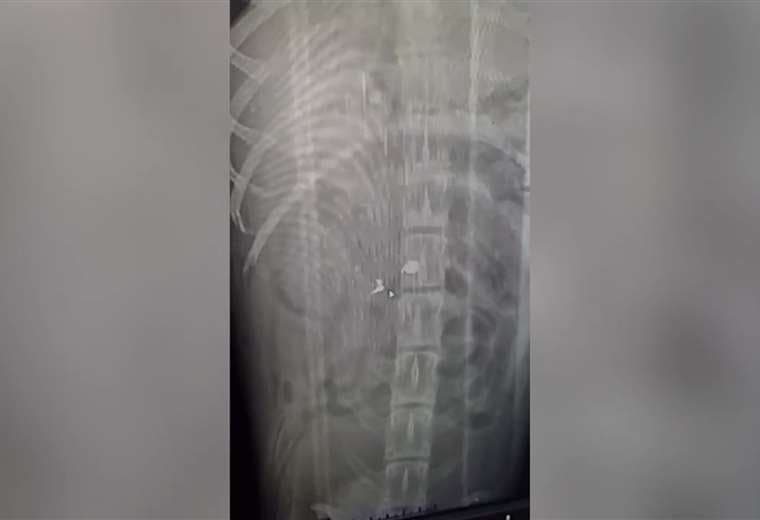

Al parecer, el animal presenta un grave problema en la médula espinal.

“Creí que tenía una fractura, pero al trasladarlo a la clínica veterinaria nos indicaron que no era fractura, sino una herida por proyectil. Ahora Canelo deberá someterse a una resonancia para determinar si el balín afectó la médula espinal.

"Si el proyectil le afectó la médula, solo hay dos cosas que podemos hacer: que una familia lo adopte para que lo cuide y le dé las mejores atenciones y, si no, hay que aplicarle la eutanasia, pero esperamos que haya buenas noticias mañana cuando nos den el resultado final de su estado de salud", agregó Villanueva.